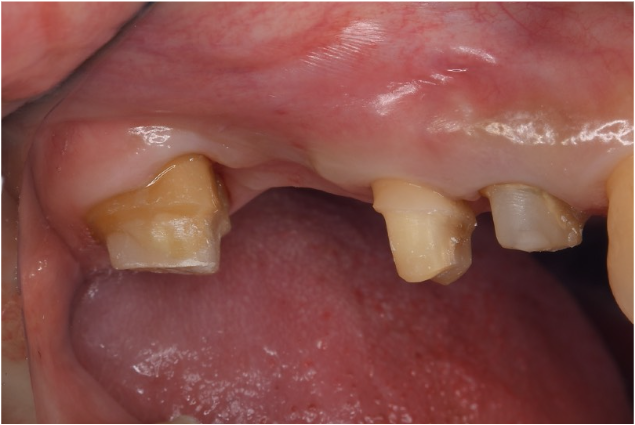

症例1

| 患者様データ | 50代 女性 |

| 来院時の主訴 | 「歯がグラグラする。噛むと痛い。」 |

| 医院の診断 | 重度の歯周病 |

| 通院期間 |

1年半 |

| 来院回数 | 10回 |

| 治療費 | 総額:200,000円(税抜)+歯周基本治療や補綴治療は保険適用診療 【内訳】 保険適用診療: 歯周病検査・歯磨きや生活習慣指導・歯石取りクリーニング・ブリッジ補綴治療 自由診療: 歯周組織再生療法200,000円(費用は範囲によって異なります。) |

| リスクと副作用 | 定期的なメインテナンスが必要、正しい歯磨き習慣・生活習慣が必要不可欠 |

| ここがこだわりのポイント!☝ | 根尖にまで及ぶ歯周病がありましたが、綿密な術前検査で神経を残せる可能性があったため神経を残して治療しました。術前検査で歯の周囲に4〜11mmの歯周ポケットがありましたが全周3mm以下に改善しました。健康な歯周組織(骨・歯肉)を獲得することができ、患者様の主訴である歯の揺れもなくすことができました。 |